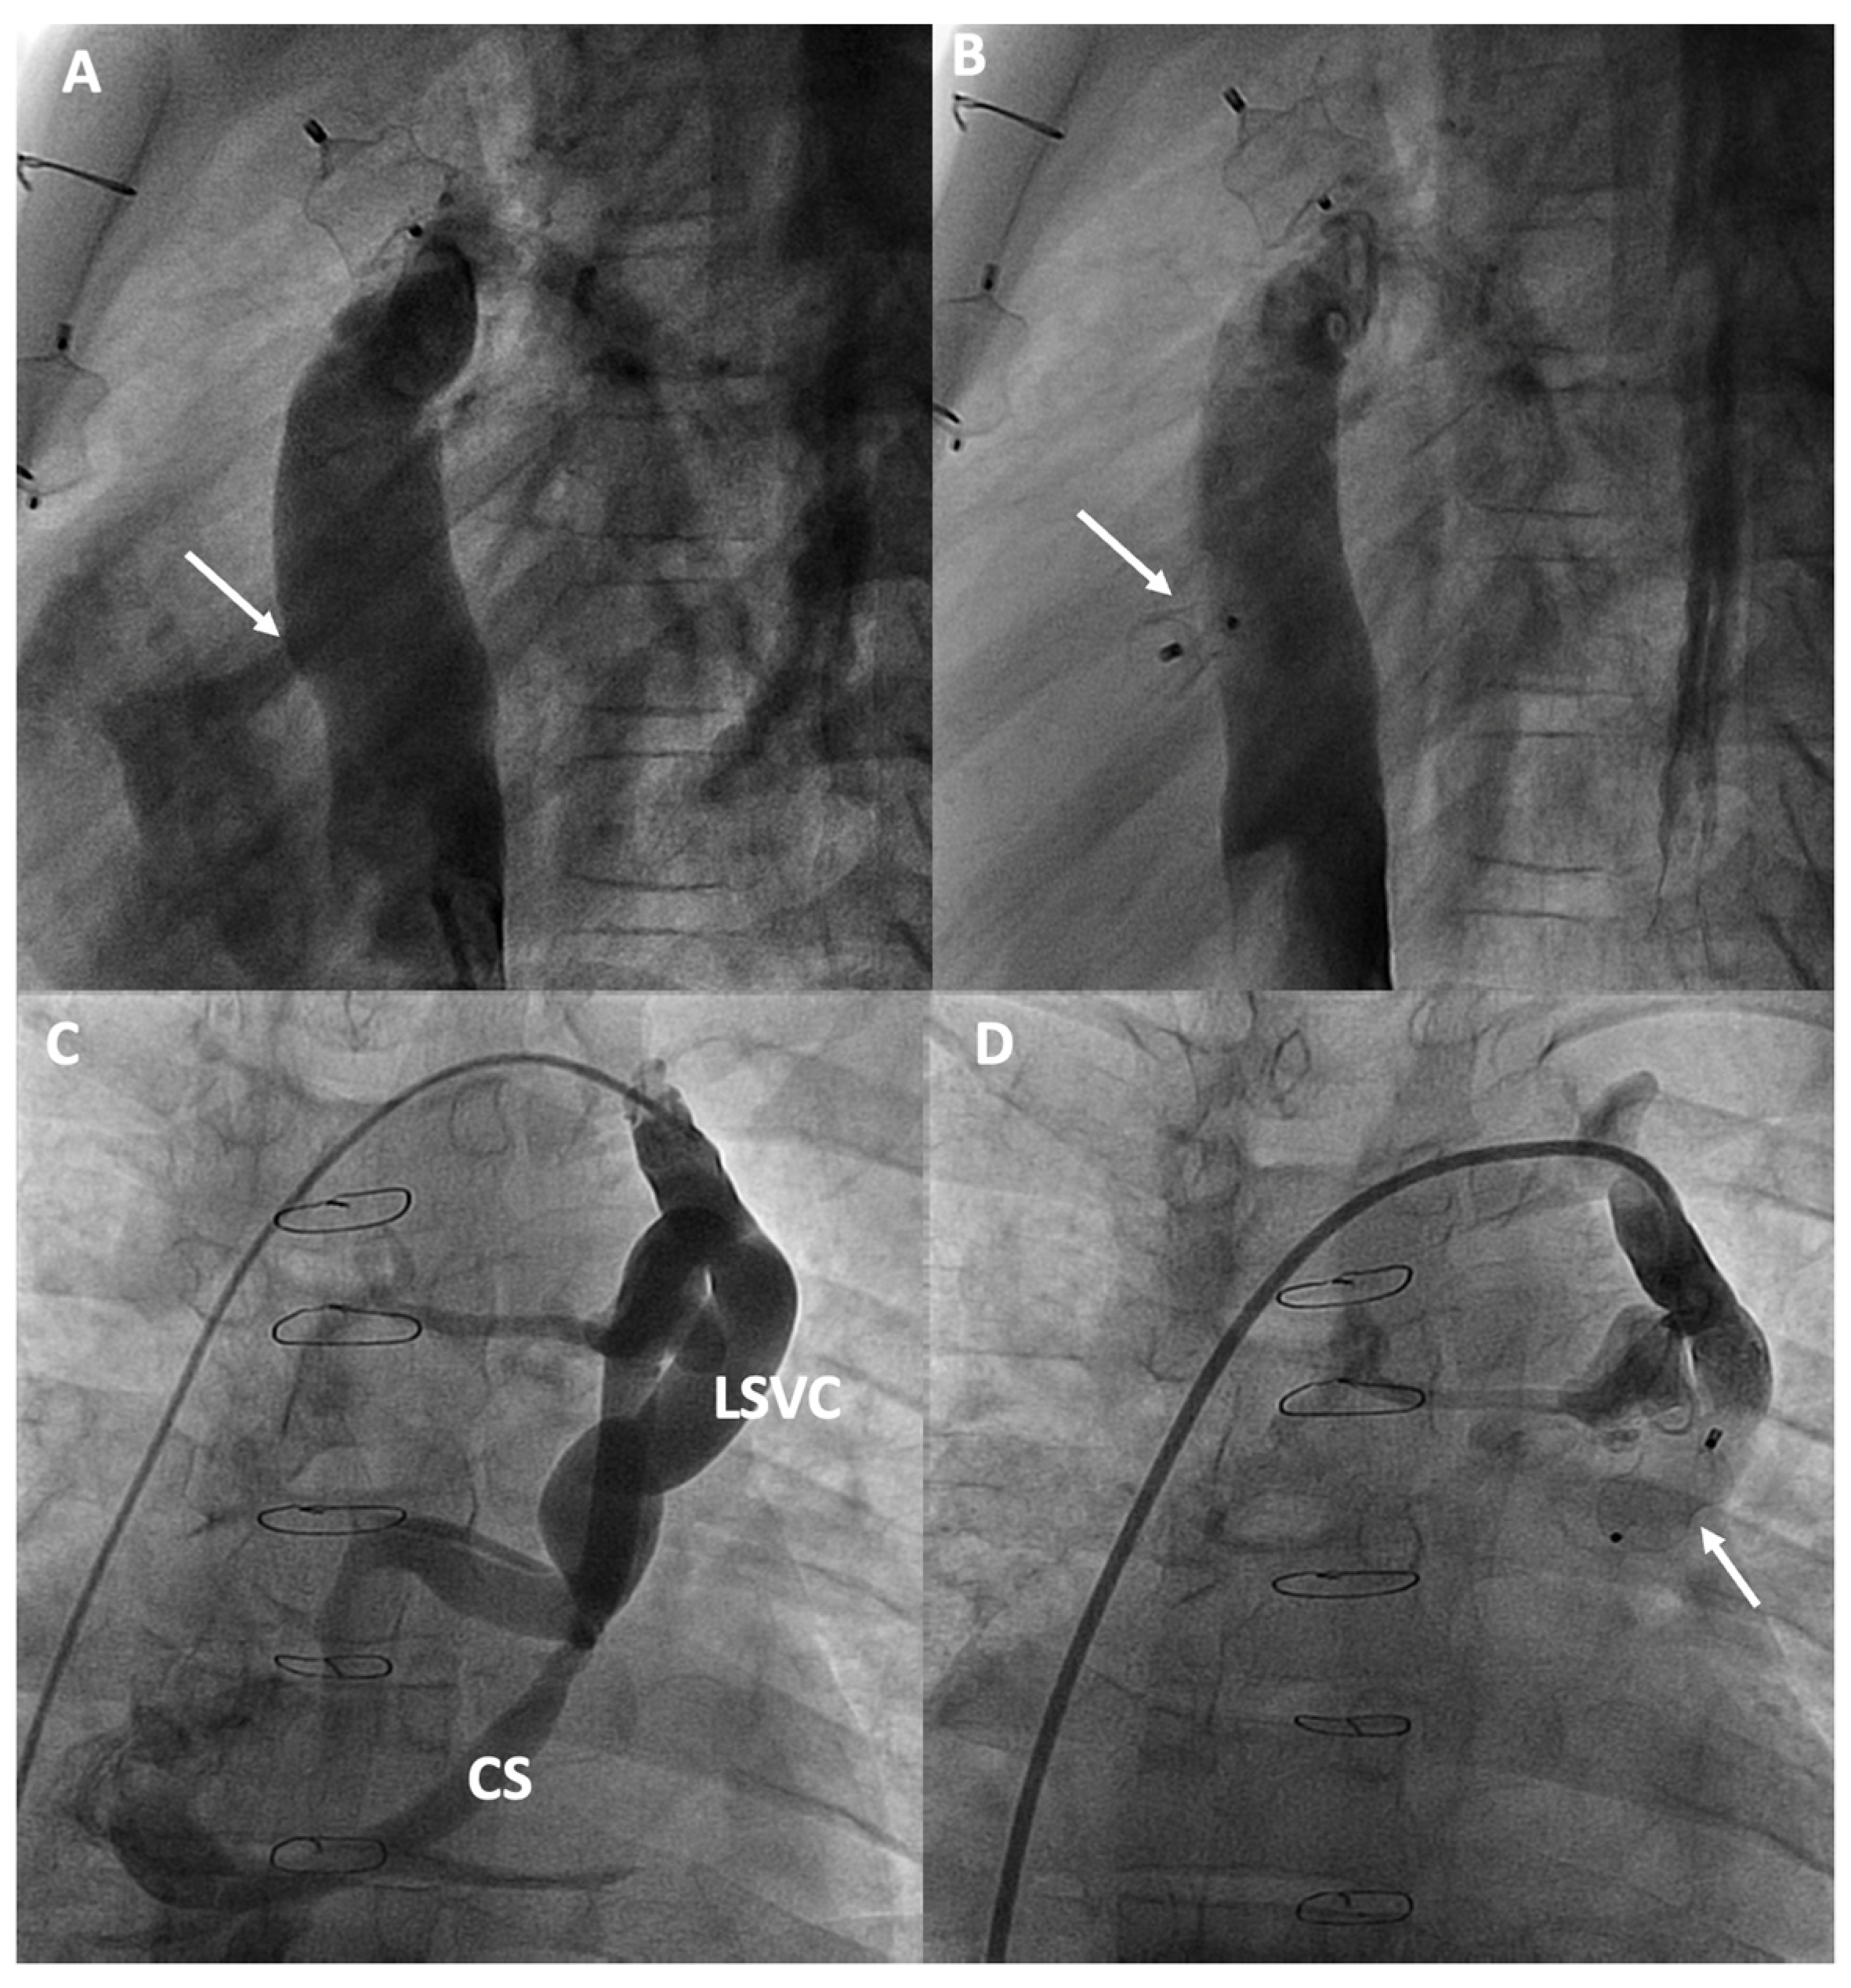

Figure 5.

Percutaneous intervention in cyanotic patients due to right-to-left shunt: (A,B) Fenestration closure; (C,D) Veno-venous shunt closure from a persistent left superior vena cava (LSVC) to the coronary sinus (CS). The arrows in each figure indicate the shunt and its closure with an occlusion device.

MAPCAs are connections between branches of the aorta and the pulmonary vascular bed, commonly found in Fontan patients, believed to form due to factors like cyanosis or reduced pulmonary flow volume. Despite MAPCAs developing to improve oxygenation in poorly perfused areas of the lung, they can lead to a higher risk of hemoptysis and volume overload on the functionally single ventricle, which can increase the risk of heart failure [73]. SPVCs are connections that typically form between the veins of the cava system or the azygos-hemiazygos system and the pulmonary veins/common atrium, creating a right-to-left shunt. Patients with persistent left superior vena cava can also produce a shunt similar to that of SPVCs through the coronary sinus (Figure 5C,D). More than half of the patients undergoing catheterization may present with SPVCs [72]. Although it is believed that these collaterals form as a result of increased central venous pressure and serve to decompress the venous system, if the shunt flow is significant, it can result in symptoms of cyanosis [74].